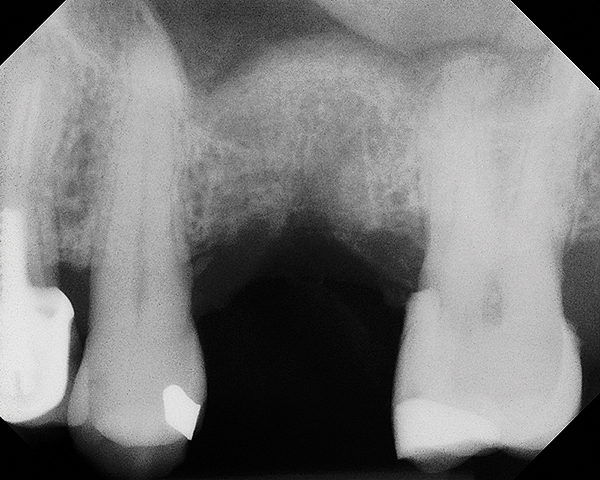

Fig 13. Case 1. Preoperative radiograph showing a ridge height of about 2 mm to 3 mm in the No. 14 position.

Figure 13

A 74-year-old man presented with only about 2 mm to 3 mm of native bone below the sinus in the No. 14 position (Figure 13). The composite graft used was an approximately 50:50 mixture of DFDBA (Bio-Oss®, Geistlich Biomaterials, www.bio-oss.com) with the addition of about 40% calcium sulfate by volume (Figure 14). The implant placed (Figure 15) was a 10-mm long, rough-surfaced, platform-shifting implant (tapered 4.2 mm to 2.8 mm), and the sinus was raised about 8 mm. The postoperative radiograph taken at 4 months (Figure 16) showed some shrinkage of the graft, but no demarcation of the old sinus floor in the area.